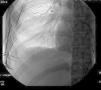

Presentamos el caso de un paciente varón de 21 años, fumador de un paquete/día, que acude a urgencias por referir dolor torácico súbito punzante en el lado derecho y disnea. A la exploración, consciente y orientado, y hemodinámicamente estable. La auscultación pulmonar objetiva un descenso del murmullo vesicular en la base de hemitórax derecho, sin evidenciar ingurgitación yugular. En la radiografía anteroposterior de tórax se aprecia un importante hidroneumotórax derecho con un colapso pulmonar moderado y un nivel hidroaéreo que llega a campo medio pulmonar derecho (fig. 1). Se inserta un tubo de drenaje torácico n.° 20 en hemitórax derecho a nivel del 5.° espacio intercostal en línea axilar anterior con drenaje de aire y menos de 100ml seroso no hemorrágico. Antes de ingresar en planta, se comprueba radiológicamente que el tubo está bien colocado y el pulmón derecho reexpande adecuadamente. A las 24h, el paciente refiere empeoramiento del estado general con abolición del murmullo vesicular en hemitórax derecho, una tensión arterial 90/60, drenaje de más de 800ml hemático y más de 400ml por hora hemático. Se realiza una TAC torácico con contraste intravenoso en el que se objetiva un neumotórax derecho con tubo de drenaje y un voluminoso nivel líquido (hemoneumotórax) que provoca atelectasia compresiva del lóbulo inferior derecho. La cavidad de neumotórax muestra un tracto compatible con bridas sin identificar el foco hemorrágico. Se completa el estudio con embolización arterial intercostal, y ante la sospecha de que el origen del sangrado sea las arterias intercostales que limitan el espacio intercostal por el que el tubo de drenaje entra a la cavidad torácica, se decide embolización de la parte distal de las mismas (fig. 2). El débito total es de 2.100ml hemático, y analíticamente presenta una hemoglobina de 8,6g/dl, precisando de transfusión sanguínea y reposición de la volemia. Durante su postoperatorio, el paciente evoluciona favorablemente, tanto desde el punto de vista radiológico como clínico, siendo retirado el tubo a los 10 días.